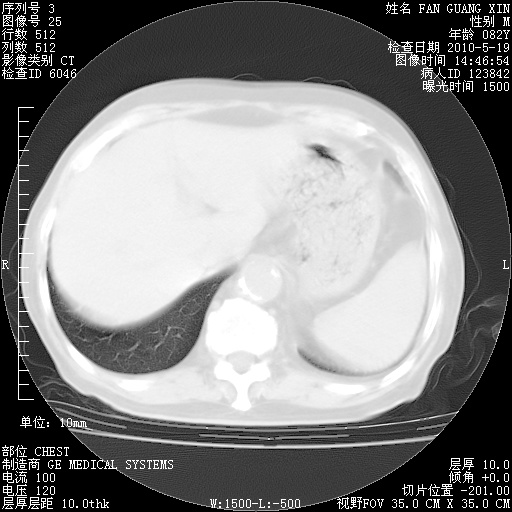

复查肺部CT,明显好转。为什么发热呢?

治疗3周后的肺部CT

治疗3周后的肺部CT纵隔窗